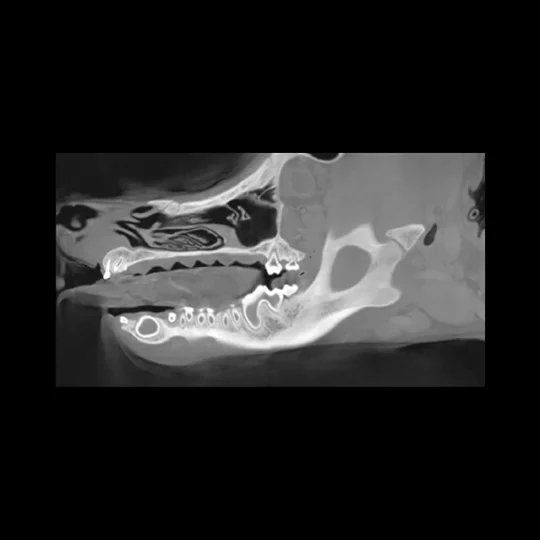

Tomografia komputerowa (TK) to nowoczesna i niezwykle dokładna metoda diagnostyczna, pozwalająca na ocenę struktur kostnych oraz tkanek miękkich głowy psa i kota. Dzięki wysokiej rozdzielczości obrazów 3D, możliwe jest wykrycie nawet niewielkich zmian, które mogłyby zostać przeoczone w standardowym badaniu rentgenowskim (RTG).

Problemów stomatologicznych i szczękowo-żuchwowych – umożliwia wykrycie zmian w obrębie zębów, korzeni, kości żuchwy i szczęki, takich jak ropnie, nowotwory, wady zgryzu czy choroby przyzębia.